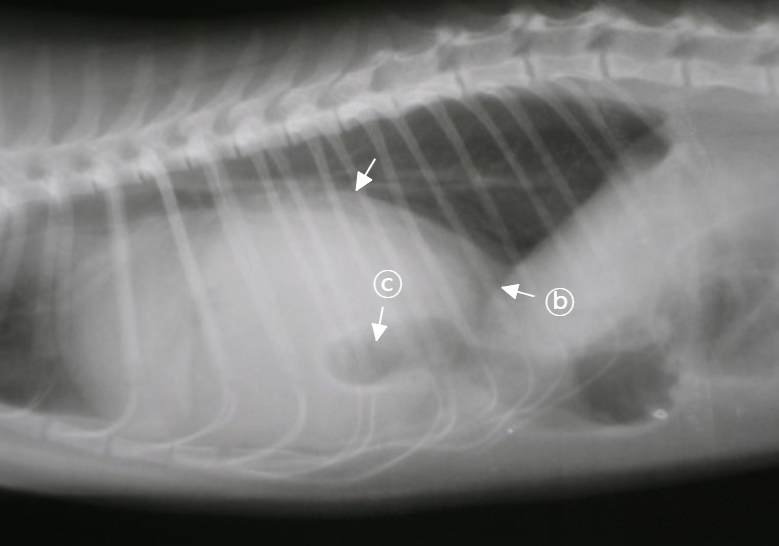

| PPDH : ๋ณต๊ฐ ์ ์ฅ๊ธฐ๊ฐ ์ฌ๋ญ ์์ผ๋ก ๋ค์ด๊ฐ โ ์ฌ์ฅ์ด ๋งค์ฐ ์ปค ๋ณด์. ![]() | - ์ ์ฒ์ฑ ์ง๋ณ์ด๋ผ ์ด๋ฆด ๋ ๋ฐ์. (PE๋ ์ด๋ฆด ๋ ์ X) - โ PPDH๋ diaphragm silluette์ด ๋ช ํํ์ง ์์. - โ ์ฅ์ ์ฐจ ์๋ ๊ณต๊ธฐ ์์์ด ๋ณด์ |